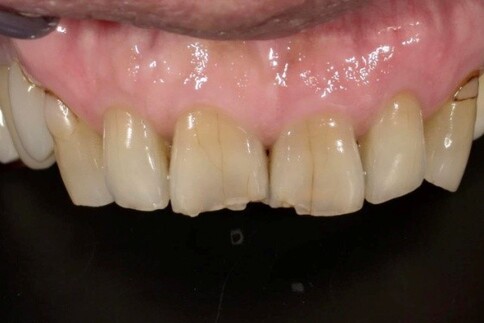

當您只有「單顆」門牙受損時,挑戰在於模仿隔壁那顆「天生的牙」。我們利用全瓷冠的高透光性創造視覺平衡,避免做出一顆看起來很新卻很突兀的假牙。

Case 2:下顎單顆假牙,齒質足夠支撐復型。